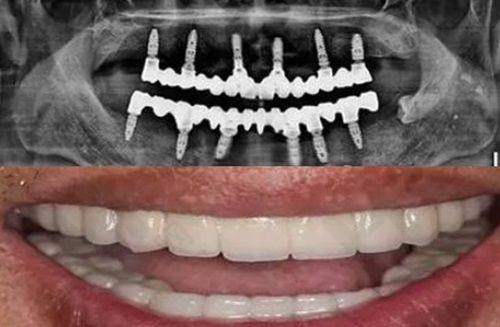

合肥瑶海松丰口腔门诊部提供的口腔诊疗服务十分全方面。种植牙领域,能满足单颗种植、多颗种植、半口种植、全口种植等不同需求;牙齿矫正方面,无论是牙列拥挤、牙列稀疏,还是龅牙、地包天等问题,都有专精的解决方案,包括儿童早期矫正检查、成人/青少年隐形矫正、自锁托槽矫正等。

该门诊部开业于 2011 年,医院面积达 800 平方米,拥有 8 个诊室、8 张牙椅以及 1 个儿童诊室。松丰口腔在多地开设了连锁机构,上海有 6 家,苏州有 2 家,合肥这家 800 多平的口腔门诊也颇具规模,并且还新筹建了 1 家大型二级口腔医院,现有员工 600 多人。

门诊部拥有一支专精的医生团队。蒋勇军作为松丰口腔种植院长,擅长 3D 数字化种植牙、即刻种植牙、牙槽骨缺损、骨增量技术、半口/全口种植牙、无牙颌种植牙、微创种植牙等,能为患者提供多种种植方案。王志勇擅长牙列拥挤、牙列稀疏、龅牙、地包天等各类错颌畸形的综合性正畸治疗。